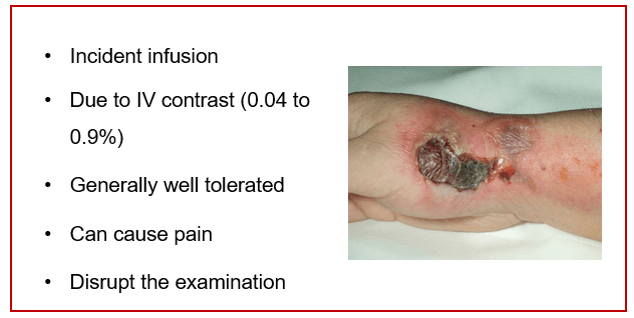

Risk of Extravasation

IV infiltration is one of the most common problems that can occur when fluid infuses into the tissues surrounding the venipuncture site. This sometimes happens when the tip of the catheter slips out of the vein, the catheter passes through the wall of the vein, or the blood vessel wall allows part of the fluid to infuse into the surrounding tissue.

Extravasation occurs when there is accidental infiltration of a vesicant that can cause blistering or chemotherapeutic drugs into the surrounding IV site. Vesicants can cause tissue destruction and/or blistering. Irritants can result in pain at the IV site and along the vein and may or may not cause inflammation. Extravasation can result in tissue sloughing, pain, loss of mobility in the extremity and infection.

The extravasation of contrast agents is an unwanted occurrence that can cause irreversible local injuries.

Extravasation of CT scan contrast media into upper extremity subcutaneous tissue is a relatively frequent complication of injection. Contrast extravasation one hour after injection showing a large area in the biceps compartment. Elevation and massage can help with the pain as well as warm compresses.